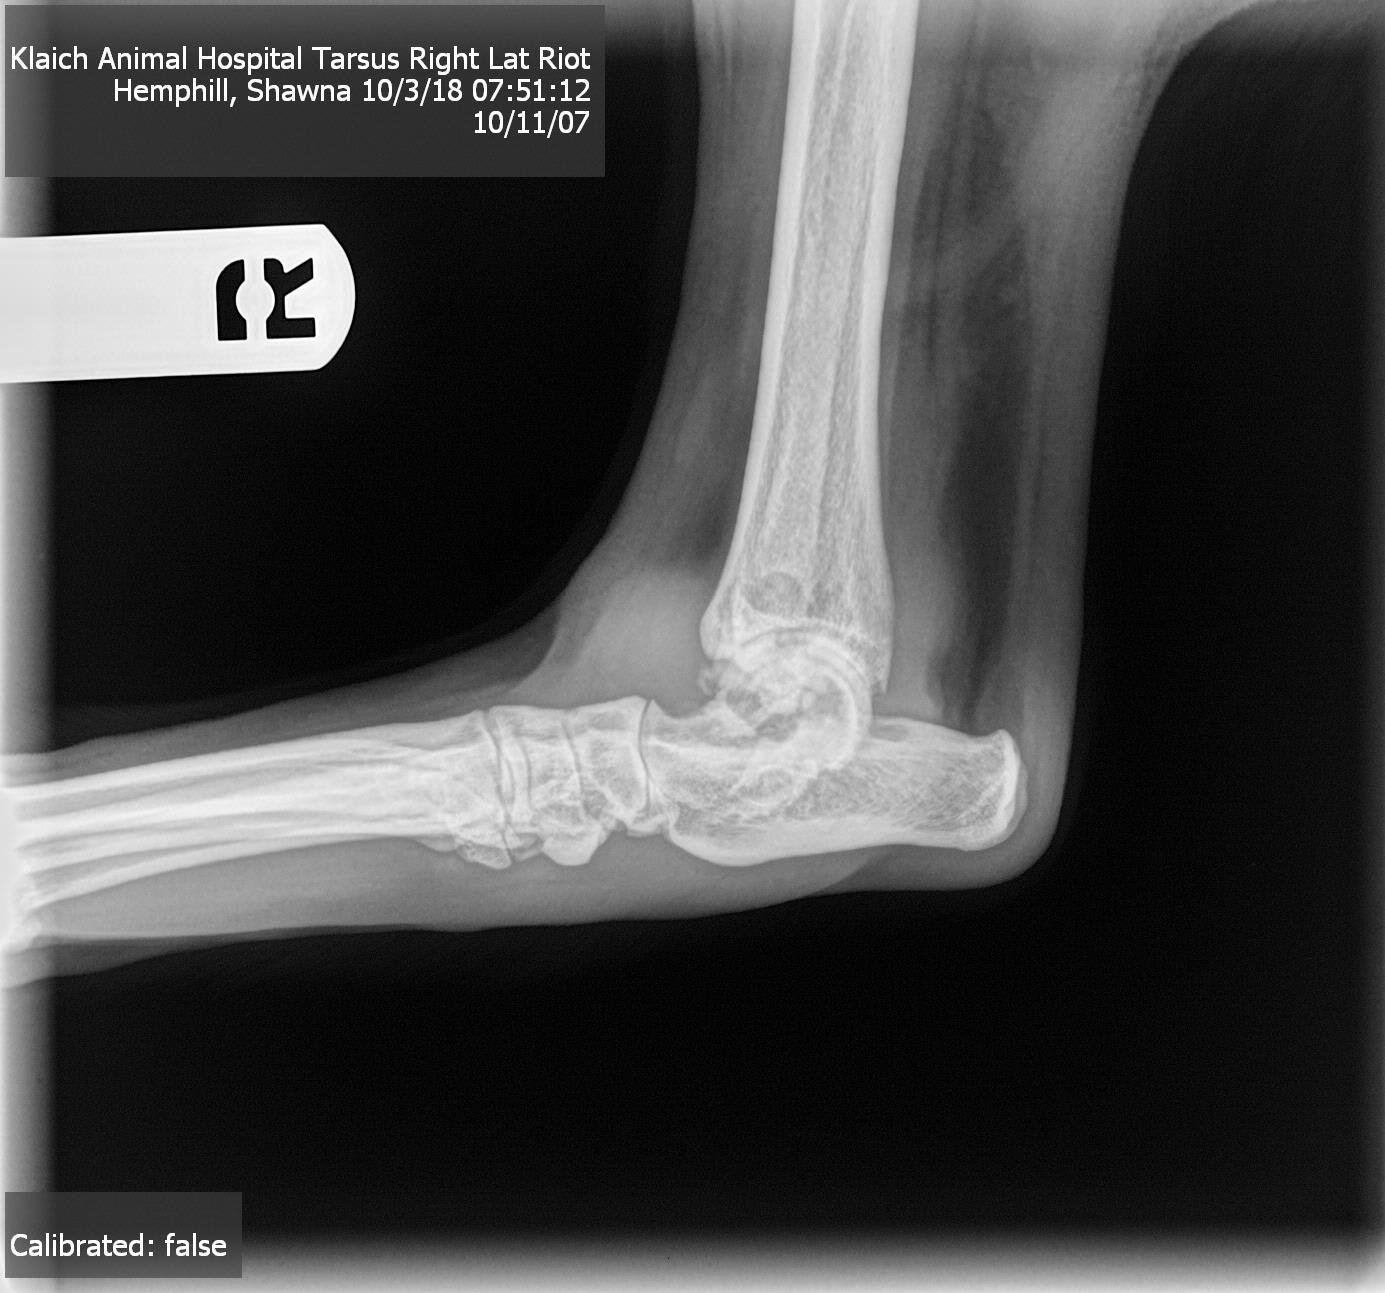

I have an 11 year old black lab. He recently went to a vet for xrays due to limping and weight loss. The vet said he has "moth eaten" bone on his leg so he suggested osteosarcoma. We did an xray of his lungs as well as blood work which both came back clear. What is wrong with my dogs leg?? He still limps badly.

Osteosarcoma can’t be totally diagnosed by an X-ray, and this doesn’t look definitive to me. I recommend taking him to an orthopedic specialist for a second opinion, and they can take another X-ray to compare with this. If it’s bone cancer the moth eaten area will probably be larger or more defined. They can also do a bone biopsy to confirm the diagnosis. He could be lame from a shoulder problem, or even pain radiating down his leg from a disc in his neck. Hopefully he is on pain medication. In my opinion the next step to be sure of the diagnosis would be to get an exam with a specialist. Thanks for using Petco Pet Education Center, formerly Petcoach to help you care for Riot.